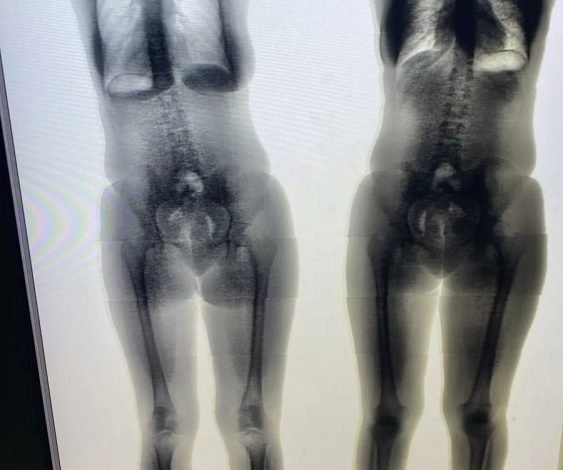

A droga foi detectada pelo body scan (escâner corporal), equipamento utilizado para identificar drogas, armas e outros objetos considerados ilícitos dentro de uma unidade prisional ou em qualquer outro ambiente protegido.

Após a detecção do entorpecente, ela foi conduzida para a sala de extração (sendo o produto extraído pela própria conduzida), foi comprovado que o corpo estranho era maconha.